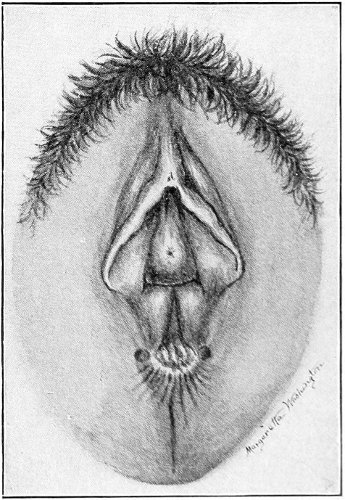

Slight Median laceration of the Perineum.—In this injury the tear takes place through the fourchette. Posteriorly it may extend as far as the sphincter ani muscle. Upward it may extend for an inch up the posterior vaginal wall. The appearance of this tear is shown in Fig. 33. It will be noted that, as this tear takes place in the median line, none of the muscles that support the perineum are involved, nor are the planes of fascia injured. The perineum is slightly split, and the insertions and origins of the muscles and the fascia are slightly separated. The supporting structures of the perineum and the pelvic floor are, however, uninjured.

Fig. 33.—Recent slight median laceration of the perineum: sutures introduced.

If this tear is detected after labor, it should be closed by the immediate operation. A slight tear involving chiefly the cutaneous aspect of the perineum should be closed by three or four sutures introduced from the outside, as in Fig. 33. The needle should be introduced about a quarter of an inch from the edge of the wound. It should not be passed parallel with the plane of the lacerated surface, but should be swept outward and then inward toward the 68 angle at the bottom of the tear (Fig. 34). It may either emerge at the angle and be re-introduced, or it may be passed directly through to the skin-margin on the opposite side of the wound. If the suture is passed in this way, there will be perfect apposition throughout the whole surface of laceration. If the sutures are improperly passed, there may result only apposition of the skin-edges.

Fig. 34.—Diagram representing the correct and the incorrect method of passing the suture for closure of slight perineal laceration.

If the laceration extends up the posterior vaginal wall, two sets of sutures must be introduced—one on the vaginal aspect of the tear, and one on the skin aspect (Fig. 35).